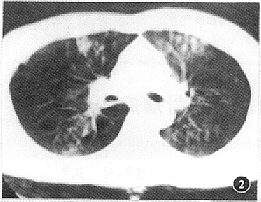

创伤性湿肺的CT表现是肺间质及肺泡的广泛挫伤和撕裂伤所引起的复合性改变。本组病例所显示的CT征象如下:(1)肺血管影增浓、模糊且粗细不均者16例(图1);(2)肺实质内散在斑点状、小片絮状稍高密度灶,边缘模糊不清者24例(图2);(3)呈磨玻璃改变的云雾状稍高密度灶,似一层薄纱复盖肺野(即“面纱征”)19例(图3);(4)大片状或呈叶、段分布的高密度灶,其内密度欠均匀,边缘不规则且模糊者20例(图4);(5)显示有大小不等、形态不规则的薄壁囊腔样低密度灶者16例(图5),囊腔内见小液平5例。上述CT表现在同一例中常混合存在。本组中CT发现有血气胸者16例,单纯血胸9例,单纯气胸6例,肋骨骨折17例,胸椎骨折3例,纵隔气肿4例,胸壁软组织积气10例,外伤性肺不张5例,肺内血肿9例。

图2 肺实质挫伤早期见散在斑点状、小片絮状稍高密度灶